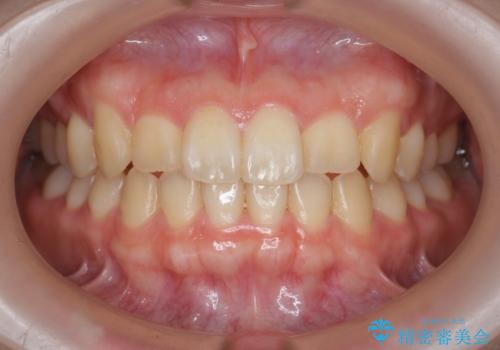

インビザラインを行う前に前歯の部分矯正を行ったことで、しっかりとねじれが取れ整った歯列へと仕上げることが出来ました。